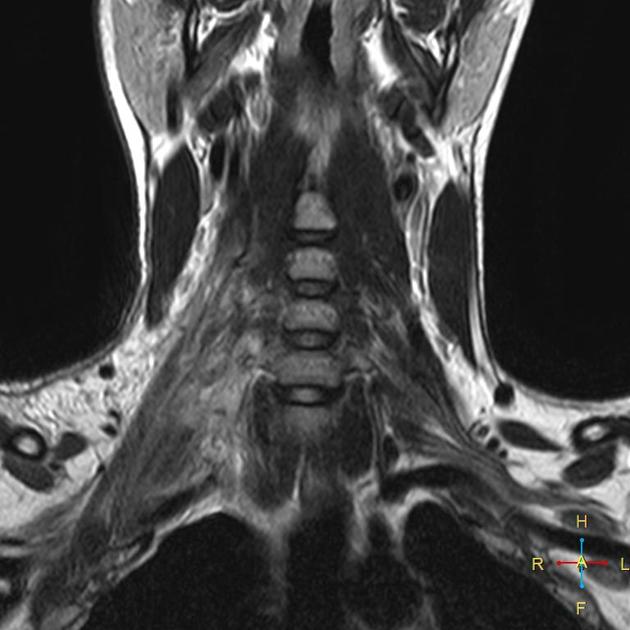

In brachial plexus, the brachial refers to the arm, and the plexus refers to a network of connected nerves. The muscles on the fingers, hand, wrist, shoulder, and arm of a baby are controlled by these nerves. Injuries to the brachial plexus can occur during childbirth.

The nerves on the brachial plexus can be damaged during difficult deliveries. These types of injuries normally occur when the baby’s shoulder gets stuck along the pelvic bone of the mother. This condition is called shoulder dystocia. It can also happen during breech deliveries when the baby is delivered feet first. In case of breech deliveries, the obstetrician may twist the baby’s head to get it through the obstruction and may cause injury in the process. These injuries include stretched nerves and complete avulsions where the nerves are detached from the sockets of the spine.

The baby may suffer from lifelong health issues as a result of brachial plexus injuries. The limbs can become partially or completely paralyzed when the brachial plexus nerves are damaged. These injuries include neurapraxia injuries and neuroma. Although neurapraxia injuries can heal naturally after several months, neuroma may cause nerve fibers to tear and may damage them permanently. Avulsions prevent the nerves from healing naturally. These injuries are severe since the nerves are permanently detached from the spine.